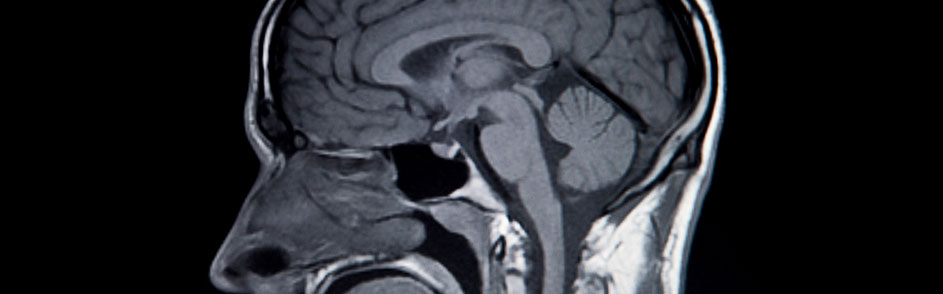

Diagnosing and Treating Disorders of the Nerves and Nervous System

The neurologists at Lima Memorial Health System deal with the anatomy, functions and disorders of nerves and the nervous system. This includes assessment, diagnosis and treatment options.

The nervous system is a complex system that coordinates and regulates body activities. It has two major divisions:

- Central nervous system: the brain and spinal cord

- Peripheral nervous system: all other neural elements, such as eyes, ears, skin and other “sensory receptors”

Our neurologists treat disorders that affect the brain, spinal cord and nerves. This includes a wide range of conditions such as: